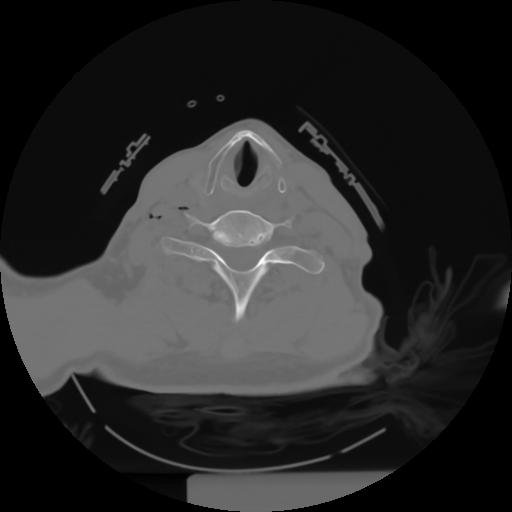

10 P.BLANDAS,,Axial,2.0,P.BLANDAS,,